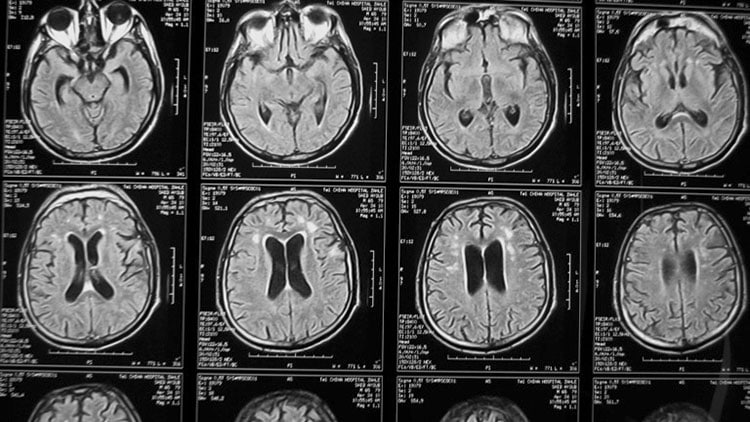

Адам Сонабенд (Adam Sonabend) и его коллеги провели первую фазу клинических испытаний (впервые на людях) на 17 добровольцах, страдающих агрессивной мультиформной глиобластомой. Как правило, лечение таких больных состоит в хирургическом удалении опухоли, остатки которой «добивают» с помощью радио- и химиотерапии. При этом приходится использовать не самые эффективные препараты — лишь бы они проникали сквозь ГЭБ.

На этот раз непосредственно после операции под череп пациентам помещали компактный прибор SonoCloud-9, создающий слабые ультразвуковые волны. Спустя одну-три недели инструмент включали на несколько минут. Параллельно пациентам в кровь инъецировали микропузырьки. Как только пузырьки достигали области действия ультразвука, они начинали вибрировать и механически раздвигали плотные слои ГЭБ.